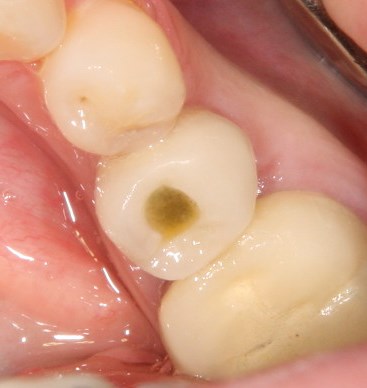

Немедленная имплантация — оптимальное решение в любой клинической ситуации